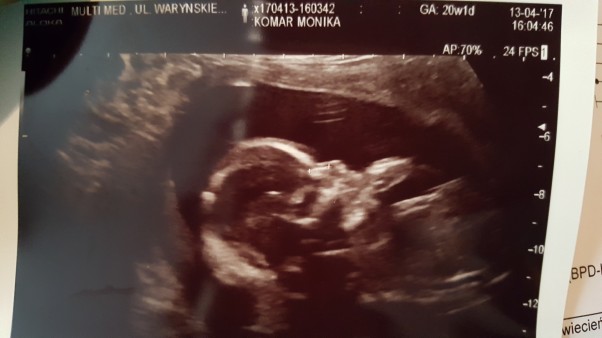

Przedstawiam Wam mojego syna Mateusza ♡♡♡ ma 257 gram jest piękny i mniejmy nadzieję że będzie całkowicie zdrowy...